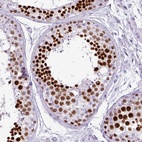

Immunohistochemical staining of human testis shows strong nuclear positivity in cells in seminiferus ducts.